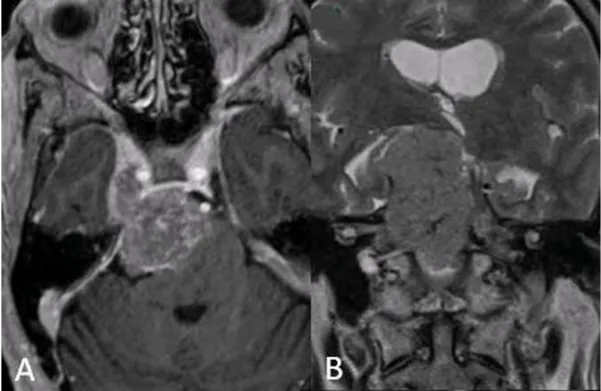

术前:A轴向增强和B矢状t2加权MRI显示右侧大岩斜坡脑膜瘤伴幕上成分,脑干受压,累及Meckel洞和右侧海绵窦。